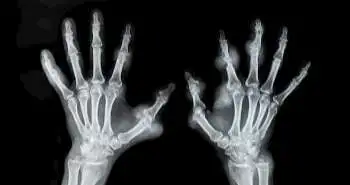

Established rheumatoid arthritis (RA) pain, a severe arthritic condition is conventionally associated with peripheral inflammation of the joints. However, it is related to early RA as well. The answer to this question is explained in the following study.

Neuropathic pain (NeP) shows significant association with established rheumatoid arthritis (RA) and affects the disease remission. However, during early RA stage, the effects of NeP was not investigated and therefore to evaluate the association between both, this study was conducted.